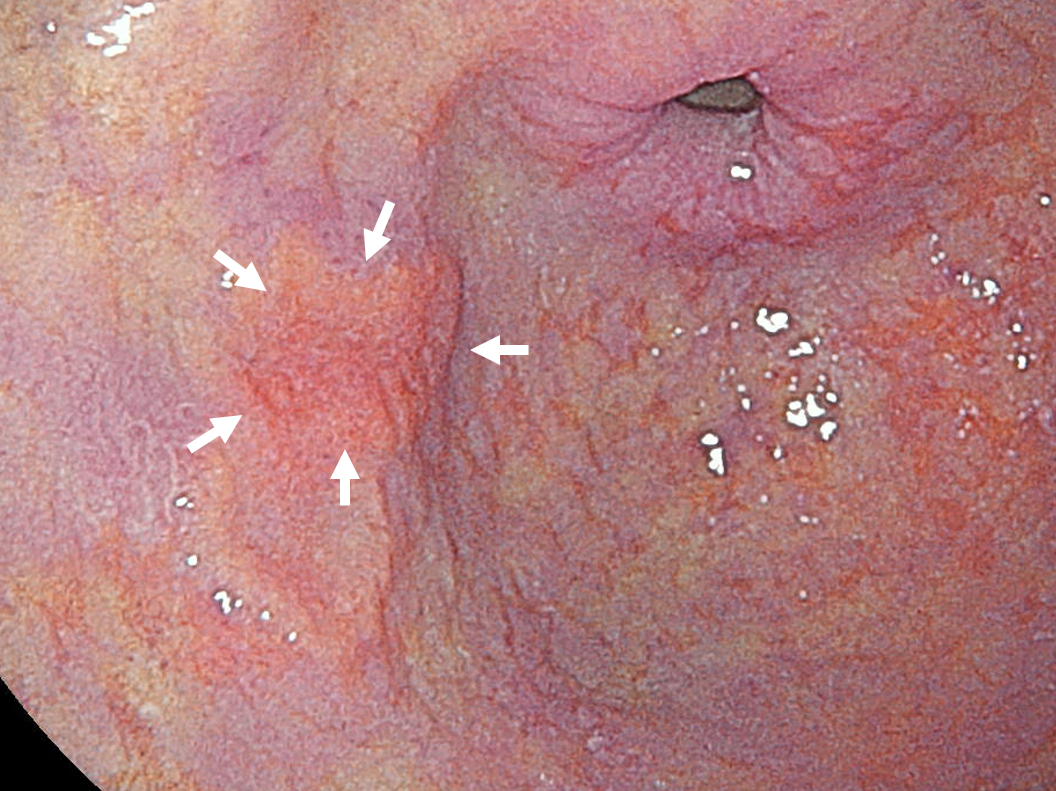

• 胃内視鏡検査:レーザーの光を用いており、早期胃癌を発見しやすくなりました。2025年に新しいカメラとなり、2mmほど細くなりましたので、苦痛も軽減されています。また、麻酔で眠った状態での検査も行っています。